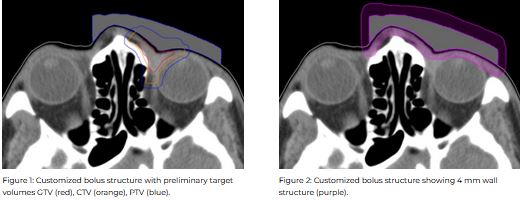

Target volumes were contoured in the Eclipse planning system (v13.6, Varian Medical). Electron plans were generated with a bolus contour modified to optimize dose distribution. The bolus contour was exported, and the rigid bolus was printed using a Taz 5 3D printer. To produce the silicone bolus, a 4 mm outside wall structure (mould) was applied to the bolus contour using Adaptiiv’s mould feature, which was exported and printed. Two-part silicone rubber was mixed, then poured into the mould and allowed to cure.

Electron plans were normalized at Dmax using 12 MeV with a dose of 6000 cGy in 30 fractions prescribed to 100%. Evaluation metrics included: Dmax to 0.1 cc of the PTV, organ at risk (OAR) Dmax for the right/left lenses, optic nerves, eyes, and the left lacrimal gland.